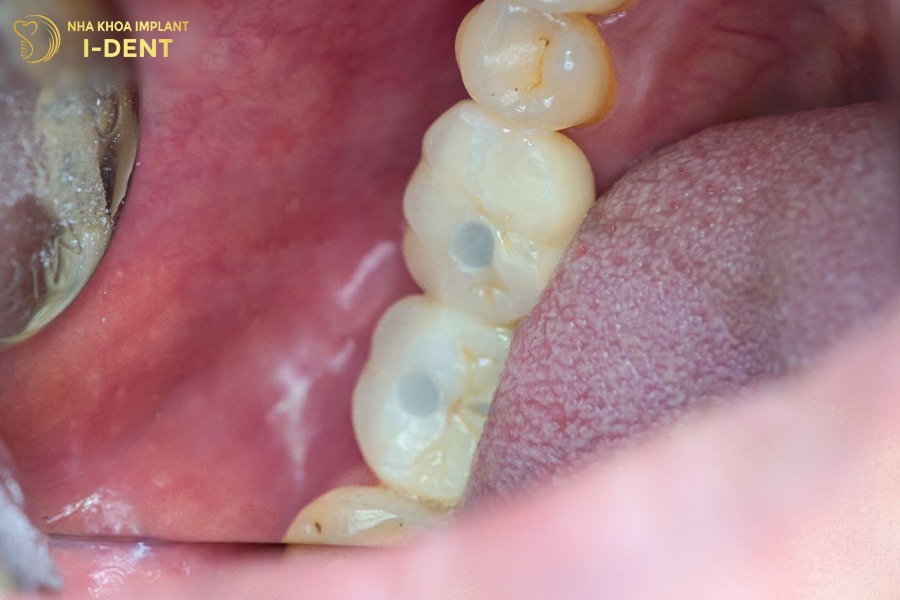

4.3 Bệnh nhân Dương Minh Đại – Cấy ghép 2 trụ Implant Mis C1 Đức

Anh Dương Minh Đại đến từ Lâm Đồng bị mất 2 răng hàm nhiều năm do bị viêm nha chu (răng chịu chức năng ăn nhai chính). Hơn nữa, anh Đại cũng có tiền sử bệnh cao huyết áp và bệnh tiểu đường, khiến cho việc điều trị phục hình răng khó khăn và phức tạp hơn những trường hợp thông thường.

Tình trạng răng ban đầu của anh Dương Minh Đại

Bác sĩ Đình Tín đã lên kế hoạch điều trị cấy ghép 2 trụ Implant tại vị trí mất răng R46 và R47 cho anh Đại. Bên cạnh đó, bác Tín đã tư vấn cho anh lựa chọn trụ implant Mis C1 Đức, đây là dòng trụ cao cấp nổi tiếng của Đức với công nghệ xử lý bề mặt tiên tiến, giúp tăng khả năng tích hợp xương và rút ngắn thời gian lành thương.

Tình trạng sau khi trồng 2 răng Implant của anh Đại